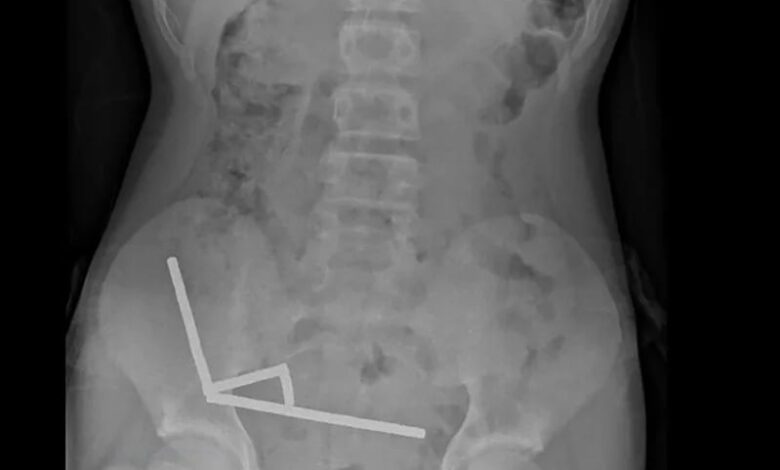

在這張紐西蘭醫學期刊(NZMJ)24日發布的未註明日期新聞照片中,X光片顯示一名青少年腸道內聚集成4條直線的強力磁鐵。法新社

儘管紐西蘭早在2013年1月就已禁止釹磁鐵銷售,但男孩仍透過線上購物平台Temu取得。X光顯示,磁鐵在男孩腸道內排列成4條直線。報告指出:「這些磁鐵位於腸道的不同部位,但因磁力作用而使各段腸道彼此沾黏。」